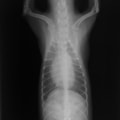

E:胸部レントゲン写真 側面像

胸部レントゲン検査において重度の心拡大と肺水腫が認められた。超音波検査では、重度の僧帽弁閉鎖不全症、三尖弁閉鎖不全症、中程度の大動脈弁閉鎖不全症を合併していることが判明した。三尖弁逆流速度から肺高血圧症が示唆された。